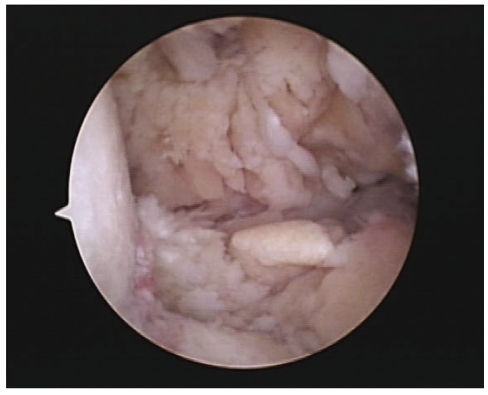

Figure 2

Arthroscopic view of the elbow joint. Severe inflammatory changes in hypertrophic synovium is observed.